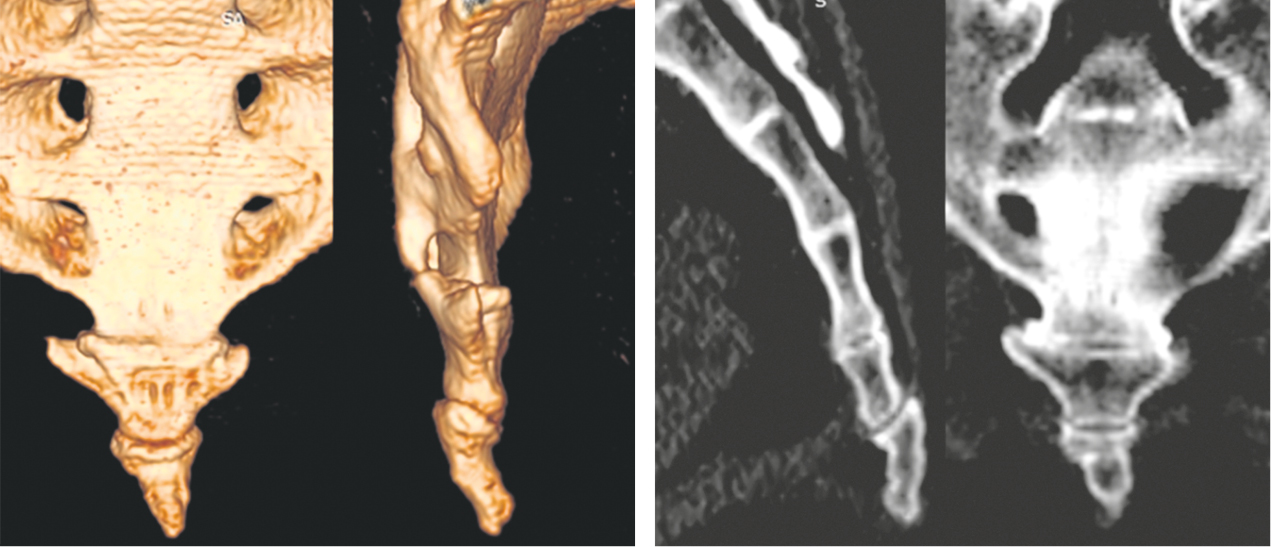

Второе клиническое наблюдение. Пациентка Б., 39 лет, находилась на лечении в клинике военной травматологии и ортопедии Военно-медицинской академии им. С.М. Кирова в июне 2019 г. Травму копчика получила 16 месяцев назад, катаясь на «ватрушке». Получала длительное консервативное лечение по поводу кокцигодинии (физиотерапия, анальгетики, блокады) с временным эффектом. По данным лучевого исследования выявлен застарелый подвывих копчика кзади и наличие костной «спикулы», спонтанный «костный блок» на уровне крестцово-копчикового сочленения (рис. 4). При ректальном исследовании обнаружена значительная подвижность копчика, сопровождающаяся выраженной болью. В клинике больной выполнена резекция копчика, послеоперационное течение без осложнений (рис. 5–8). Пациентка выписана на 4-е сутки после операции. Индекс ВАШ через 1 месяц после операции составил 2 балла, а при дальнейшем наблюдении — 1 балл. По шкале удовлетворенности операцией — «полностью удовлетворена».

Рис. 4. Компьютерная томография крестца и копчика пациентки Б. до операции

Fig. 4. CT of the sacrum and coccyx of patient B. before surgery